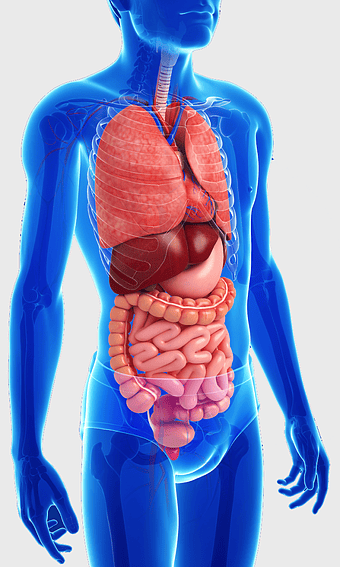

614x1024px

human gastrointestinal tract anatomy, human digestive system illustration, gastrointestinal disease symptoms, human body organ diagram, internal organ visualization, medical anatomy study, digestive health awareness -

human digestive system, gastrointestinal tract anatomy, liver function, stomach and intestines, digestive health, internal organs diagram, human body systems -

human digestive system illustration, gastrointestinal tract diagram, human body organ system, labeled digestive system, digestive anatomy chart, human internal organs, alimentary canal visualization -